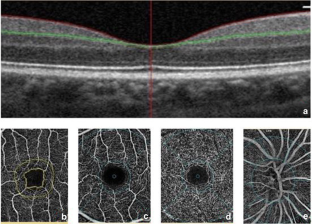

Fig. 1